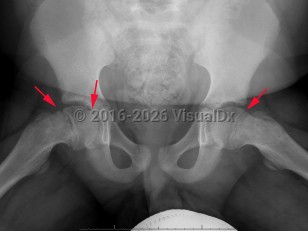

Slipped capital femoral epiphysis

Another classification tool is the Southwick slip angle classification. This uses the epiphyseal-diaphyseal angle, which can be measured on both anteroposterior (AP) and frog-leg lateral pelvis imaging. SCFE can be classified as mild if the angle is less than 30 degrees, moderate if between 30 and 50 degrees, and severe if greater than 50 degrees.